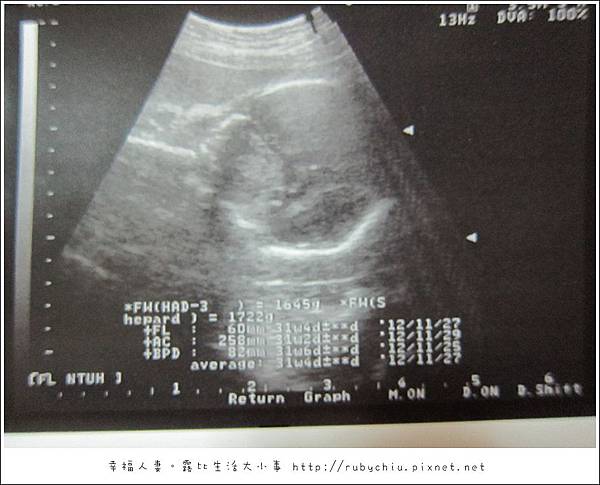

距離照4D時是27W1D "紀念品"當時的體重是1057公克。

而上次給曾醫生產檢是23W5D, 當時"紀念品"才630公克。

然後就開始照超音波了...雖然心情有點差... 但看到螢幕上的"紀念品" 又忘了剛剛醫生說的話。

醫生就說 baby很正常,目前大小31週5天!講完又回到看診間看了我的病歷..發現我的週數才29W5D

然後就說"碧如,妳才29W5D小朋友31W5D,這個月又胖了4.8公斤" 然後就對著老公說

照例!補一下29W的超大肚照!裏面裝著31W的紀念品妹妹啦!